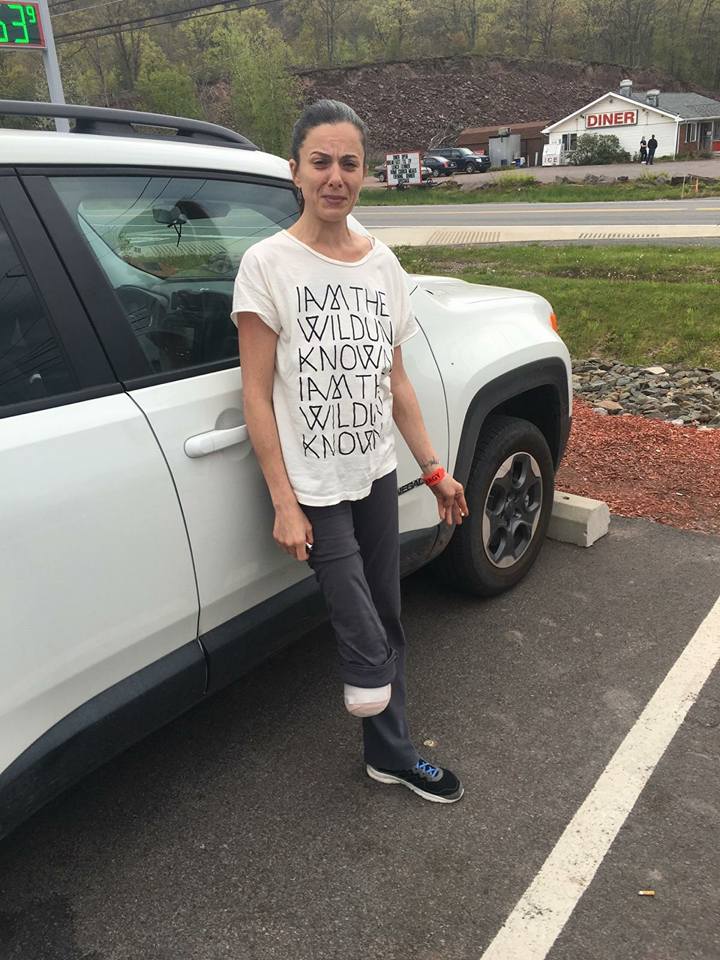

Six days post-amputation—Wednesday, May 18—I was transported to the rehab facility in an ambulance-like transport van. When I arrived, I asked for a walker. They gave me a walker with no wheels and walked me a long distance to the back of the building, where my room was.

When he finally arrived, he was panicked. I had no walker, no crutches, nothing. I hadn’t been formally discharged—I’d been transferred from the hospital to rehab, where I was supposed to receive mobility equipment. I got none of it. I made him stop anywhere so I could get a pack of cigarettes. I was not ok.

We went back to the hospital where I had just been discharged, looking for some type of mobility device. No one would give me a walker or crutches. To this day, I’ve never officially complained about any of it, though I probably should—even nearly ten years later.

Before my amputation, I’d attended one amputee support group, but I’d been turned off by the political tone and lack of supportive energy. Still, I called the group leader and explained what had happened—that I was going home instead of rehab and had no mobility aids. He said, “I’m bringing you a walker.” And he did. That small act was life-saving.

We returned to my apartment, which wasn’t ready for me at all. Area rugs were everywhere. My favorite person rolled them up, cleared paths, and set me up as best he could. Later, he told me that night was the most scared he’d ever been for me, leaving me alone, fifty-five miles from anyone, with no car, no license, no neighbors I knew, no groceries, and no leg! I wasn’t supposed to be home yet. I was supposed to be in rehab for weeks.

I have lived alone six days after my amputation, almost ten years. No witness to the highs and lows, no comfort from another human, no help—no one. The first seven months were the hardest. I often went, on average, two weeks without a visitor because my apartment was far from my friends, many of whom did not have cars. I suffered a fracture on the fibula of my residual limb, five weeks to the day post amputation, which complicated everything, including fitting a prosthetic. I was going through full menopause, divorce, and amputation all alone and simultaneously. Those months changed me profoundly: I was transformed through a combination of grace and grit.